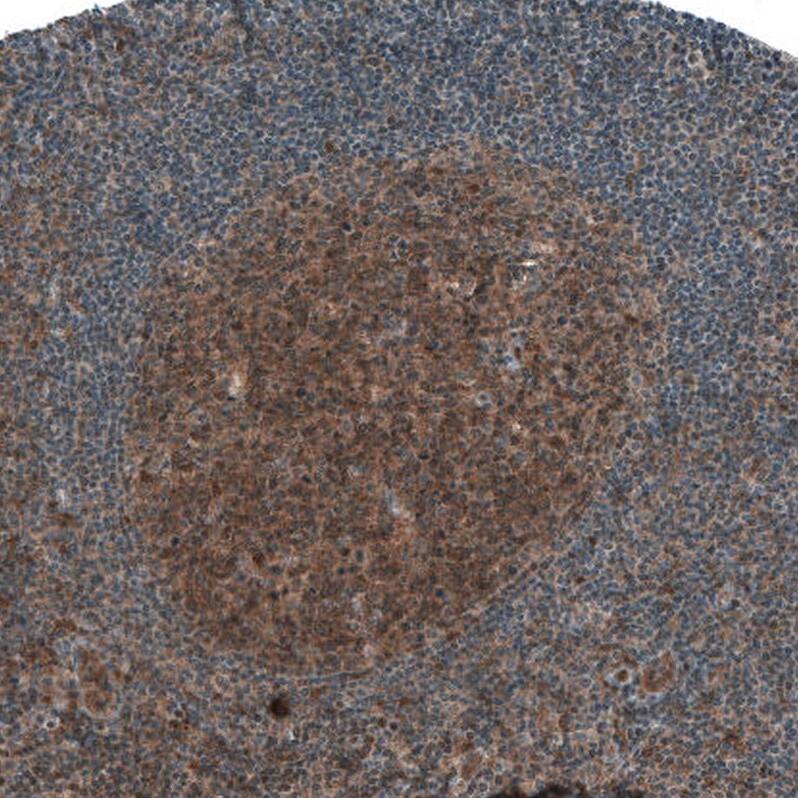

Staining of human tonsil shows moderate cytoplasmic positivity in germinal center cells.